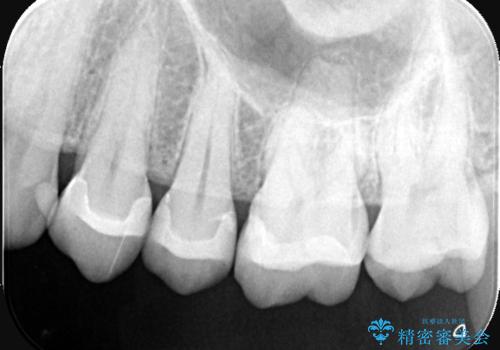

【セラミックインレー】虫歯になった詰め物部分を修復

- 前医で治療された詰め物の部分に、定期検診で虫歯が見つかったため、セラミックインレーにて修復治療を行いました。

接着時にはラバーダム防湿を行っています。